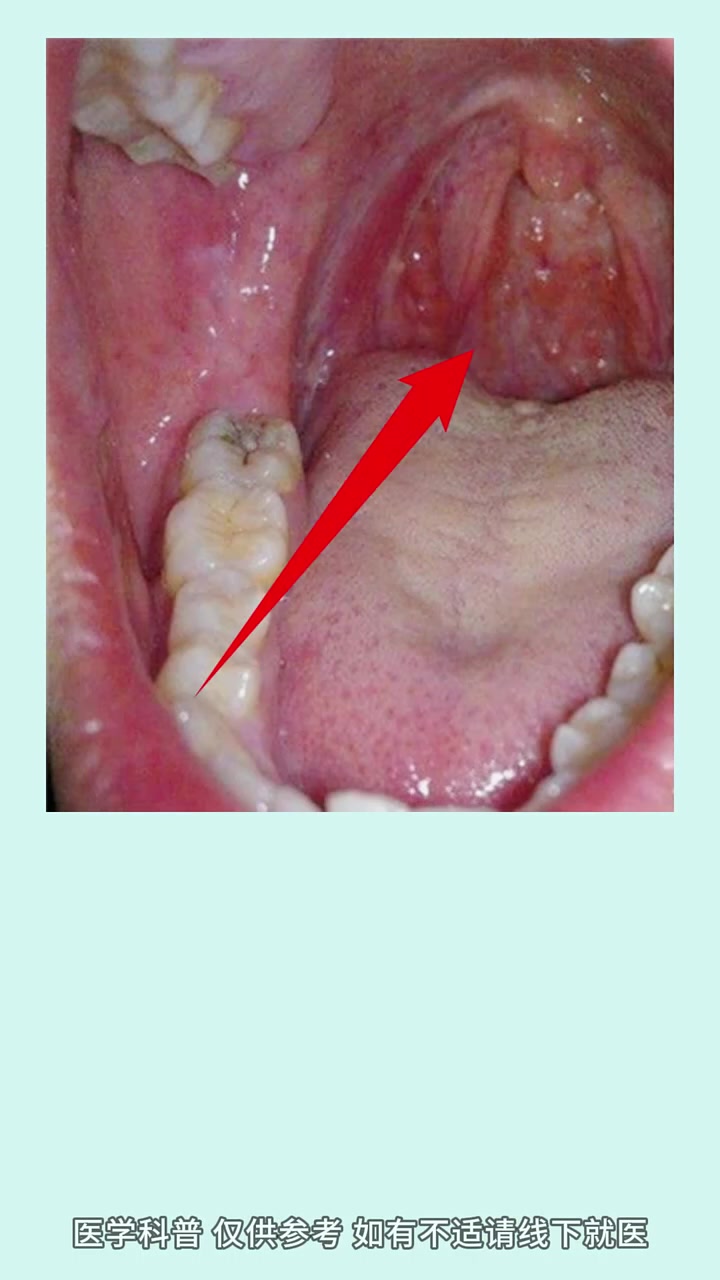

舌根部息肉增生图片视频

舌头下面息肉图片 舌根息肉图片 牙龈增生图片息肉 息肉图片早期 舌头根部长肉颗 正常舌下系带肉芽图片 舌头后部有小肉疙瘩 舌头根部长肉疙瘩 舌头肉芽组织增生图片 舌根部息肉增生图片